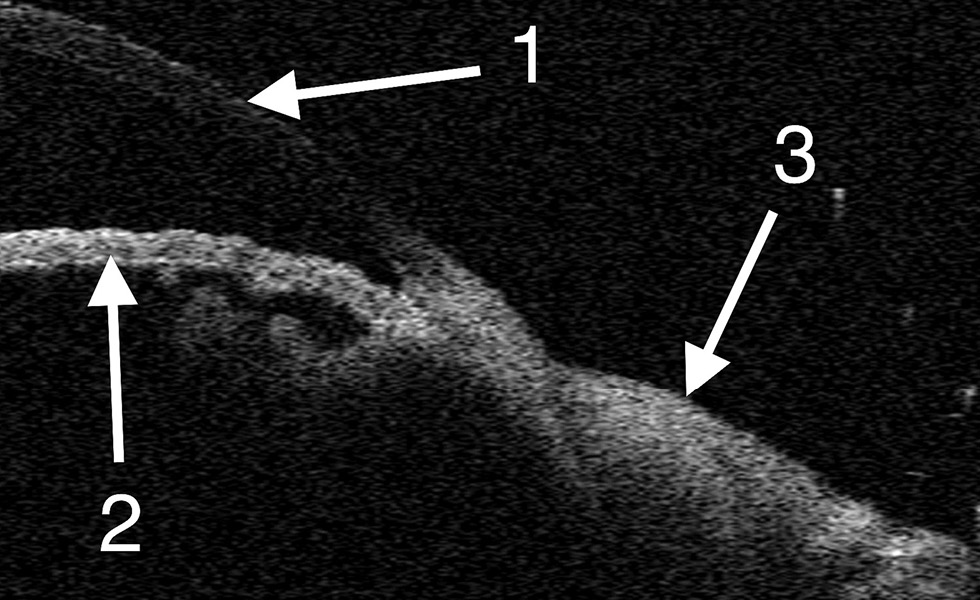

При динамическом наблюдении особенно тщательно следили за состоянием роговицы, пересаженных лоскутов конъюнктивы и обнажённого участка склеры. В раннем послеоперационном периоде клинически у всех животных отмечали отёк и гиперемию тканей конъюнктивы. Признаков токсикоаллергической реакции не наблюдали ни в одном из случаев. В зоне дефекта определяли плотную белесоватую ткань с бугристой поверхностью. По данным УБМ на 7-е сутки после операции в области аппликации клея и фиксации конъюнктивальных лоскутов визуализировали гиперэхогенную линейную пресклеральную структуру — это слой клеевой плёнки. Кроме того, выявляли локальное утолщение конъюнктивы со снижением эхогенности в зоне вмешательства (рис. 1). По данным ОКТ были получены изображения интактной роговицы и неравномерно утолщённой конъюнктивы в зоне хирургического вмешательства (рис. 2).

Рис. 2. Оптическая когерентная томография на 7-е сутки после операции: 1 — роговица, 2 — радужка, 3 —конъюнктива в области операции.

Fig. 2. Optical coherence tomography on Day 7 post-surgery: 1, cornea; 2, iris; 3, conjunctiva in the area of surgery.